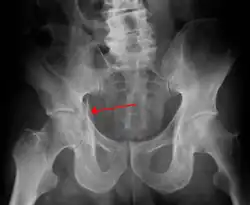

Fractures of the acetabulum occur when the head of the femur is driven into the pelvis. This injury is caused by a blow to either the side or front of the knee and often occurs as a dashboard injury accompanied by a fracture of the femur.[1]

The acetabulum is a cavity situated on the outer surface of the hip bone, also called the coxal bone or innominate bone. It is made up of three bones, the ilium, ischium, and pubis. Together, the acetabulum and the head of the femur form the hip joint.